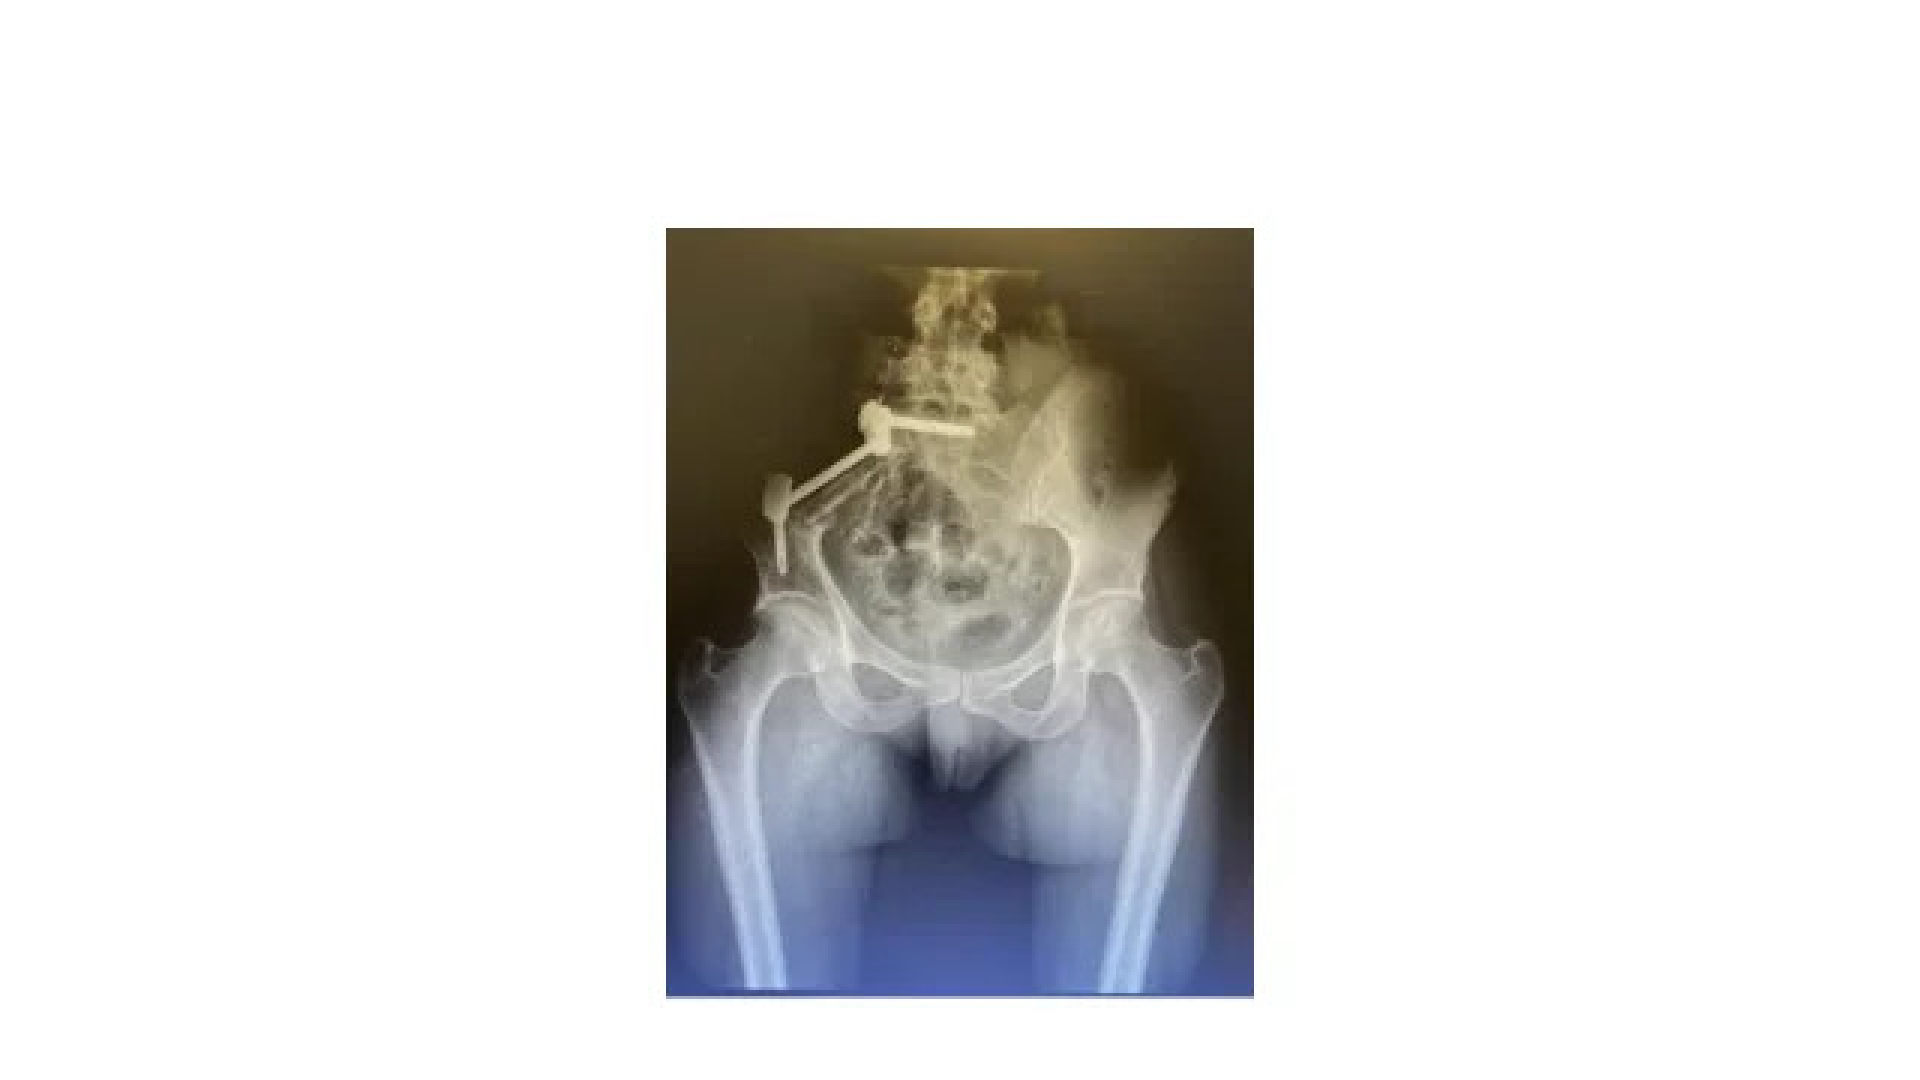

Osteosarkom malign bir kemik neoplazmıdır. Çocukluk çağında en sık görülen primer kemik kanseridir.

Primer tümörler genellikle uzun kemiklerin metafizinde meydana gelir ve yaklaşık %60’ı diz ve çevresinde ortaya çıkarlar. Bu durumdan etkilenenlerin büyük çoğunluğunu çocuklar ve ergenler oluşturur.